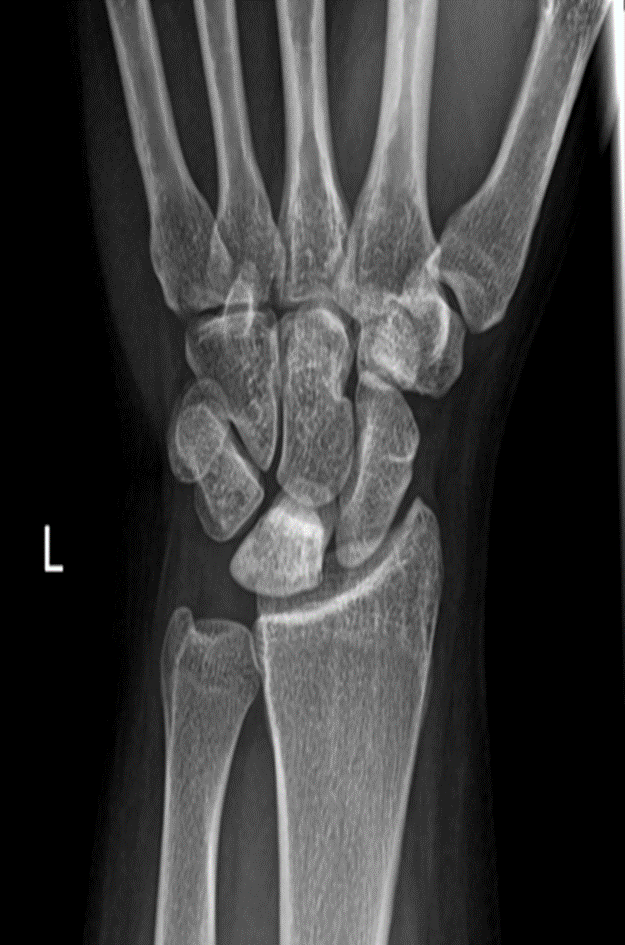

Plain x-ray of Avascular necrosis of lunate